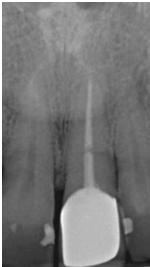

患者之後於96/11/08在右下第一小臼齒與植體間有膿胞產生,並於97/02/21確認右下第一小臼齒有根裂的情形,因此在97/02/29拔除此牙;經過將近半年後,於97/09/23放置一顆植體於此位置

97/02/21 確定根裂時拍的片子

97/02/21

97/09/18 拔牙半年後安排右下第一小臼齒植牙前

97/09/23 右下第一小臼齒植牙完成時